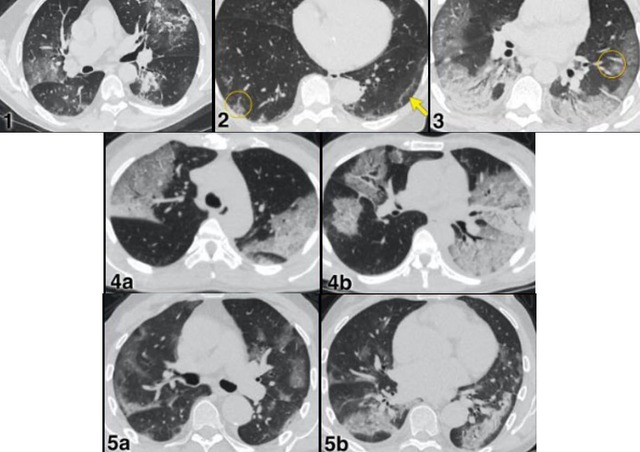

Hình ảnh CT cho thấy tổn thương phổi lan tỏa do sốc nhiễm khuẩn tụ cầu vàng.